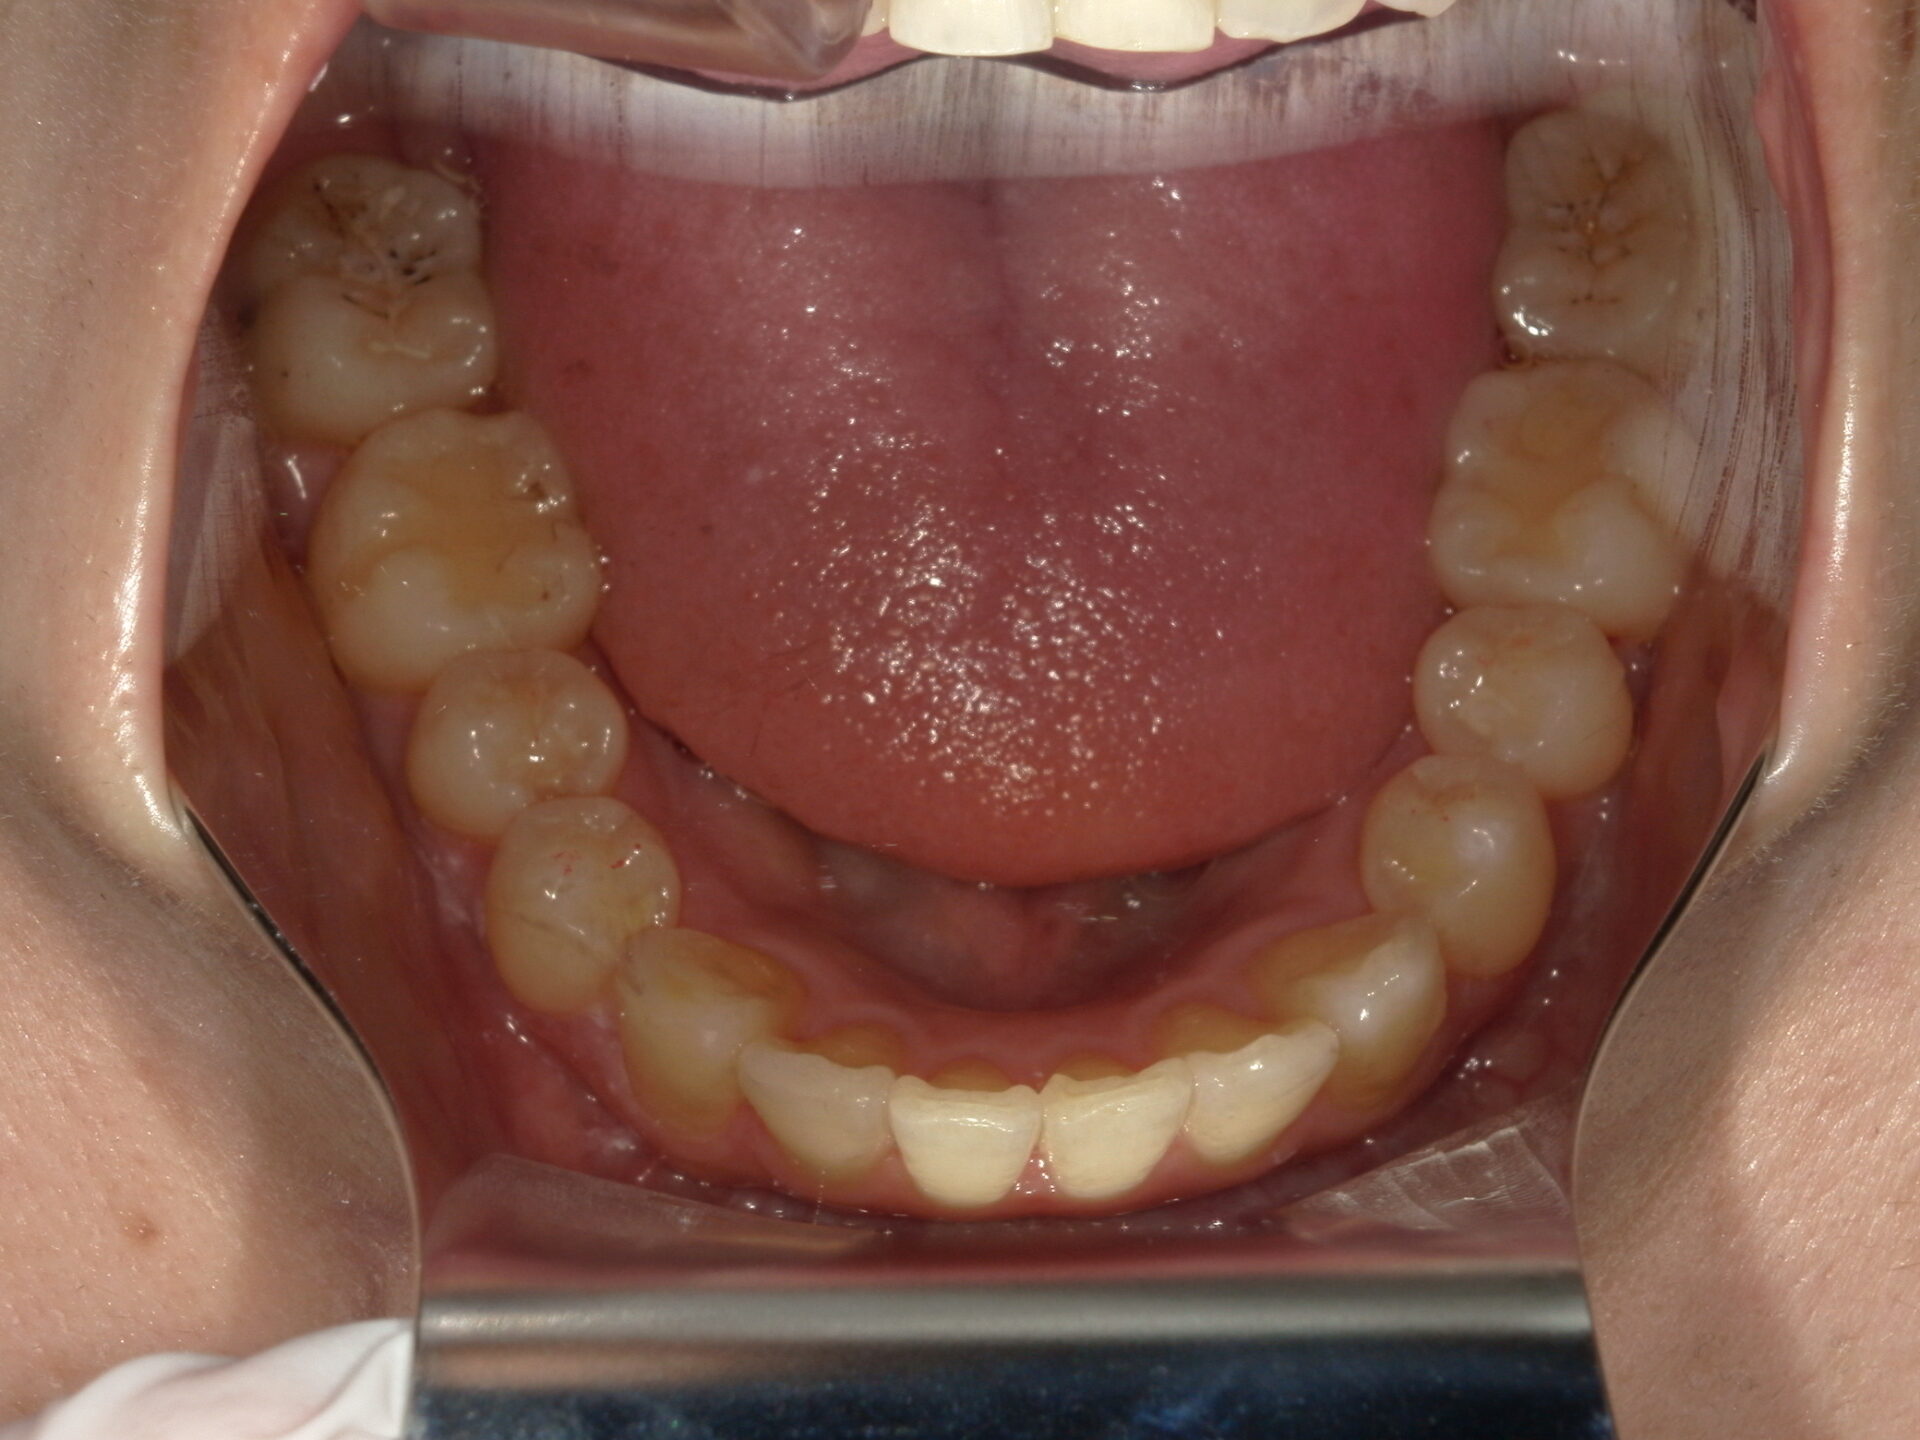

before

患者さんの年齢 20代 女性 症状 見た目が良くなりたい 治療内容 マウスピース矯正治療 費用 90万(税抜) 治療期間・回数 治療期間2年半、通院回数20回 メリット スマイルラインが綺麗 デメリット・リスク 期間がかかることがある 患者さまの声 見た目が綺麗になった - マウスピース矯正